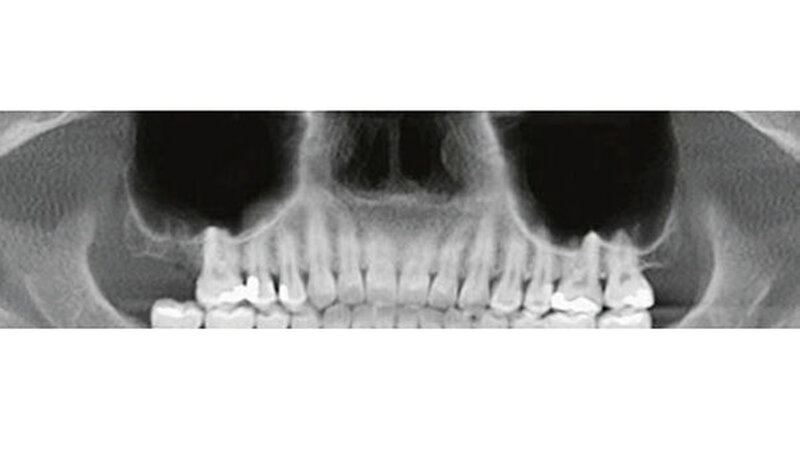

Die erste postoperative Kontrolle erfolgte nach vier Tagen. Die Patientin war beschwerdefrei, und intraoral zeigte sich eine stadiengerechte Wundheilung. Die klinische Kontrolle war ohne pathologischen Befund. Die Rachenhinterwand war frei und zeigte keinen Schleim oder Eiterabsonderung des Sinus maxillaris. Zehn Tage postoperativ stellte sich die Patientin mit einer ebenso regelrechten Wundheilung vor, die Nähte konnten entfernt werden. Bei der 4-Wochen-Nachkontrolle zeigte sich eine feine, nicht entzündete Narbe im Bereich des Zugangs. Die röntgenologische Kontrolle zeigte eine gut belüftete rechte Kieferhöhle auf dem halbseitigen OPT.